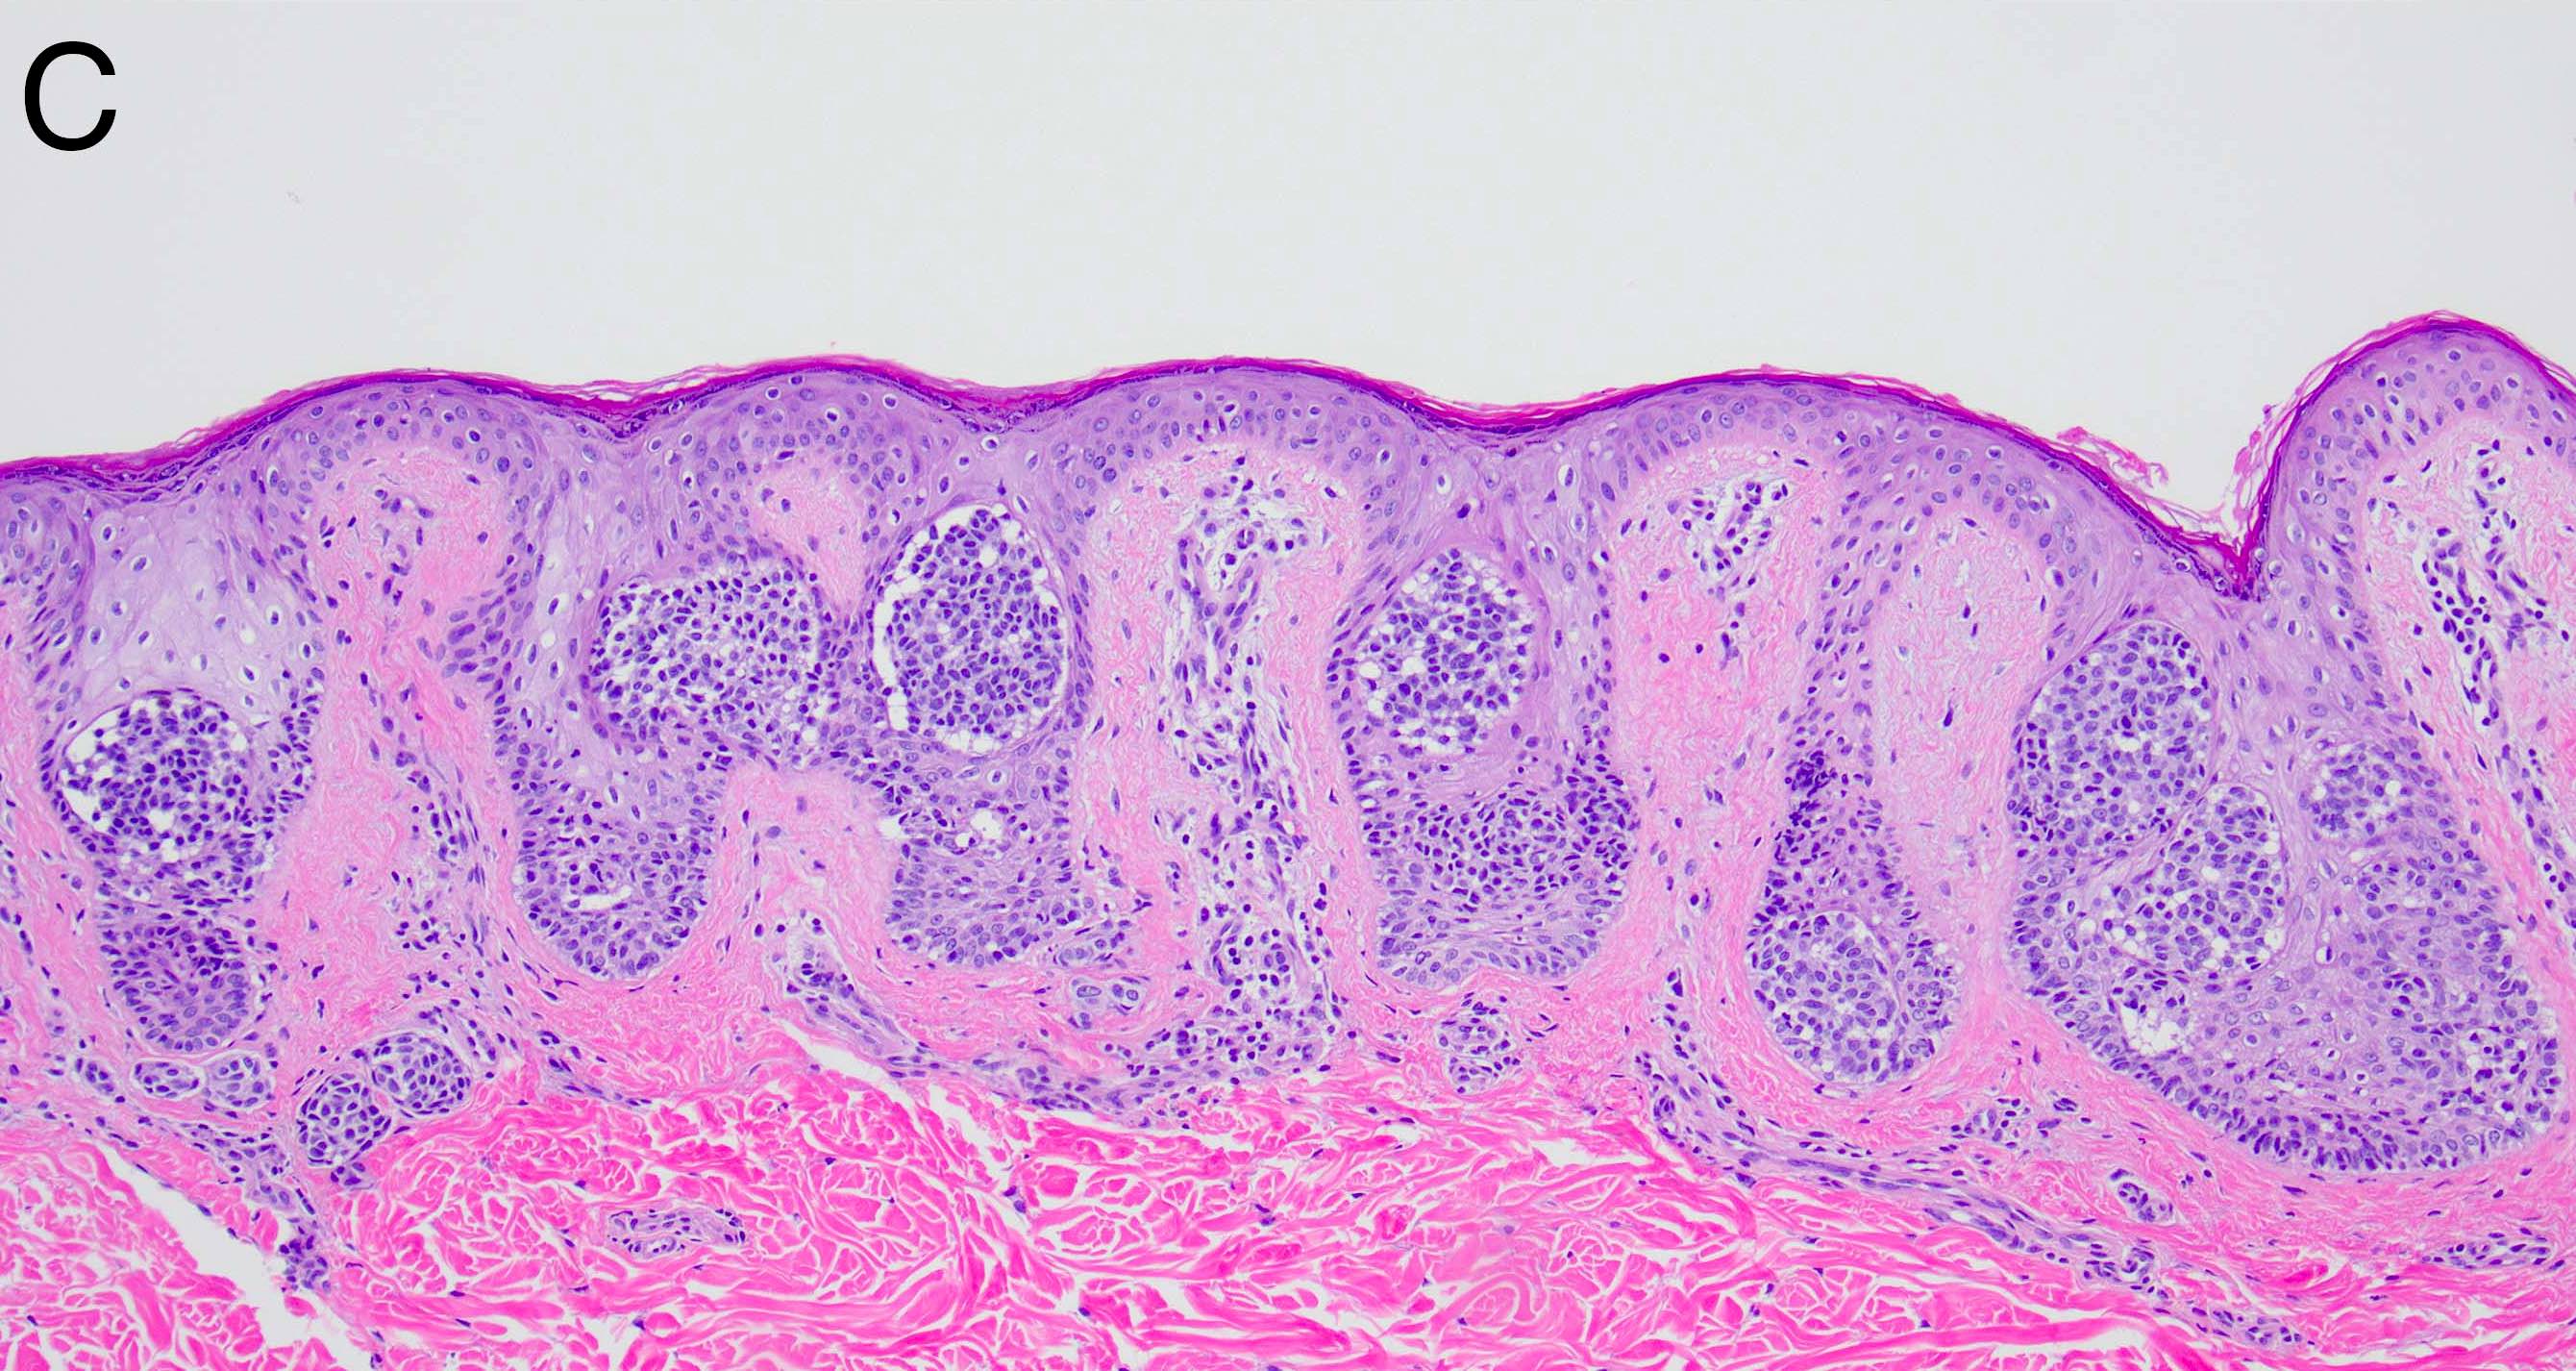

- Melanocytic nevi of the acral skin (Am J Dermatopathol 2016;38:867):

- May have unusually prominent pagetoid or lentiginous growth pattern

- Should not display high grade cytologic atypia

- Dermal component should display well formed nests and maturation with descent

- Cytologic atypia and mitotic activity should not be seen in dermal component

- There is an absence of lentiginous involvement of the crista profunda intermedia

- Banal appearing nests along eccrine apparatus are an acceptable feature in acral nevi

- Melanocytic nevi of the breast (Am J Dermatopathol 2016;38:867):

- May contain large irregular dyshesive nests in close proximity to one another

- Junctional nests may not be centered and can be placed within inter-rete spaces and along sides of rete

- Nests may have variable pigmentation (results in globules seen on dermoscopic exam)

- Nests may have prominent horizontal streaming resulting in rete blunting or epidermal effacement

- Cytologic atypia is common

- Maturation with melanocyte descent should be retained

Microscopic (histologic) images